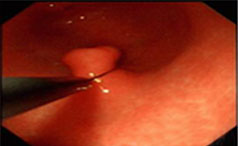

胃息肉的存在会干扰胃的正常消化功能,从而导致消化不良症状的出现。此外,胃息肉如果增大或破裂,会刺激胃壁,引起疼痛和呕血等症状。胃息肉也可能破......【详情】

常见症状:上腹隐痛、腹胀、不适

无痛性便血、脱垂

【导语】胃肠息肉的发生与多种因素有关,应该定期进行胃肠镜检查,以便及......【详情】